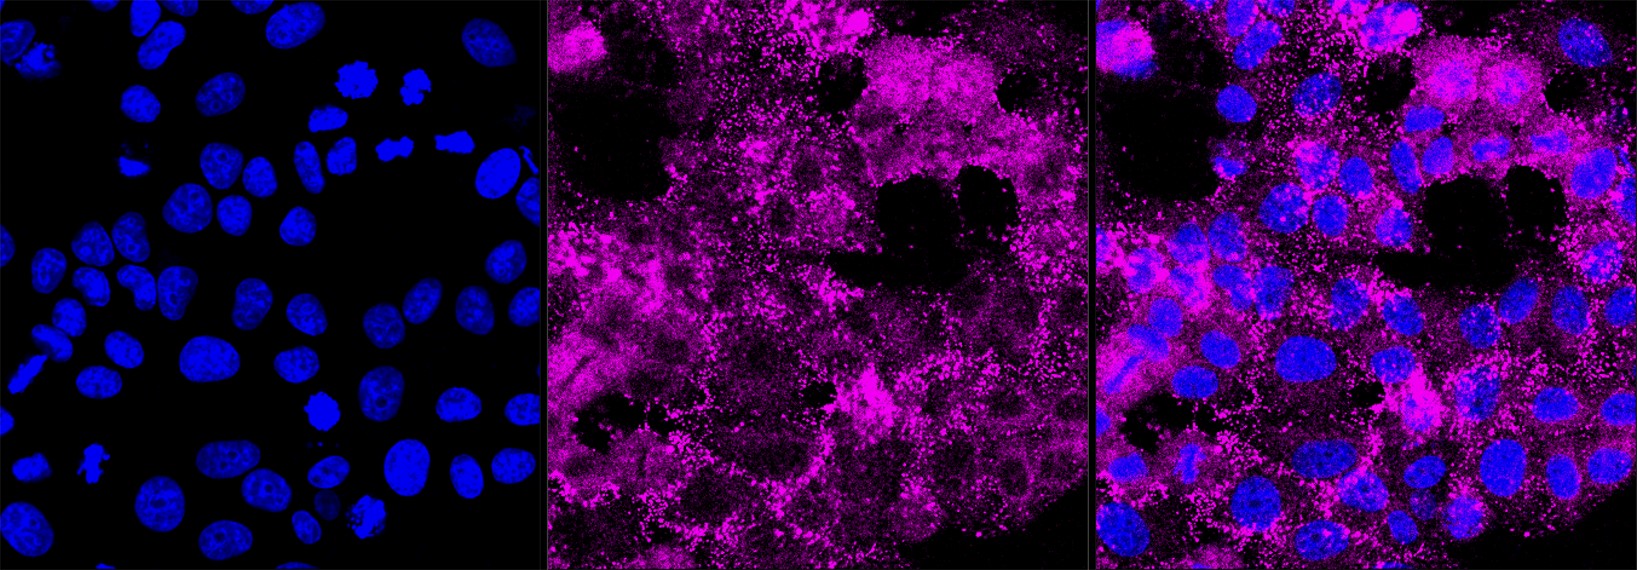

• Immunocytochemical staining of HepG2 cells with Histone deacetylase 6 antibody. Nuclei were stained blue with DAPI; Histone deacetylase 6 was stained magenta with Alexa Fluor? 647. Images were taken using Leica stellaris 5. Protein abundance based on laser Intensity and smart gain: Medium. Scale bar, 20 μm.